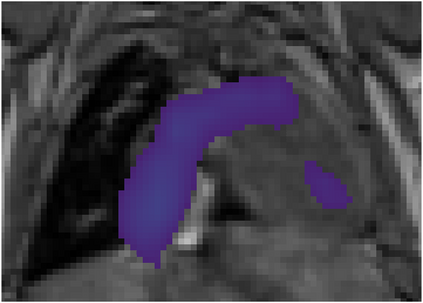

Various imaging modalities allow for time-dependent image reconstructions from measurements where its acquisition also has a time-dependent nature. Magnetic particle imaging (MPI) falls into this class of imaging modalities and it thus also provides a dynamic inverse problem. Without proper consideration of the dynamic behavior, motion artifacts in the reconstruction become an issue. More sophisticated methods need to be developed and applied to the reconstruction of the time-dependent sequences of images. In this context, we investigate the incorporation of motion priors in terms of certain flow-parameter-dependent PDEs in the reconstruction process of time-dependent 3D images in magnetic particle imaging. The present work comprises the method development for a general 3D+time setting for time-dependent linear forward operators, analytical investigation of necessary properties in the MPI forward operator, modeling aspects in dynamic MPI, and extensive numerical experiments on 3D+time imaging including simulated data as well as measurements from a rotation phantom and in-vivo data from a mouse.